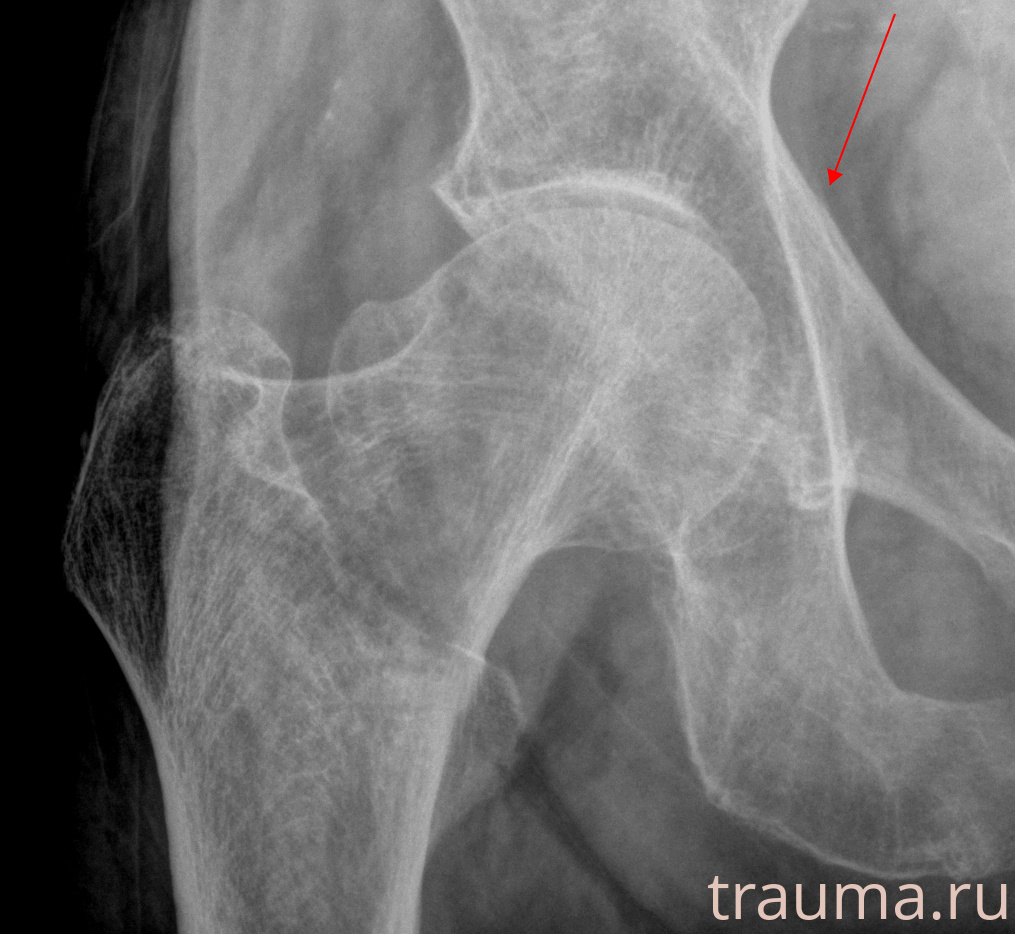

Рентгенограммы

Рентген на дому: по вашему адресу приезжает врач-рентгенолог, травматолог-ортопед с мобильным рентгеновским аппаратом, проводит диагностику травмы или заболевания, делает необходимые рентгенограммы, дает рекомендации по дальнейшему лечению. Получить качественные снимки в домашних условиях возможно благодаря уникальной методике, разработанной МосРентген Центром для института  Склифосовского